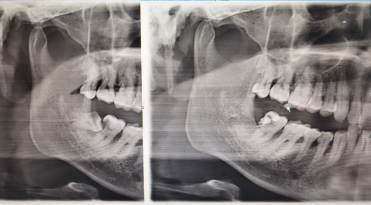

泰州四院近期开设复杂牙拔除专病门诊,专注于拔除各类复杂牙齿,汇聚经验丰富的口腔科医师团队,配备微创拔牙器械、超声骨刀、数字化影像等先进设备,为患者提供安全、舒适、精准、无菌的拔牙诊疗服务。

1.精准术前评估:通过CBCT三维影像技术清晰显示牙齿位置、牙根形态及与周围神经血管、上颌窦的关系,制定个性化拔牙方案规避手术风险。